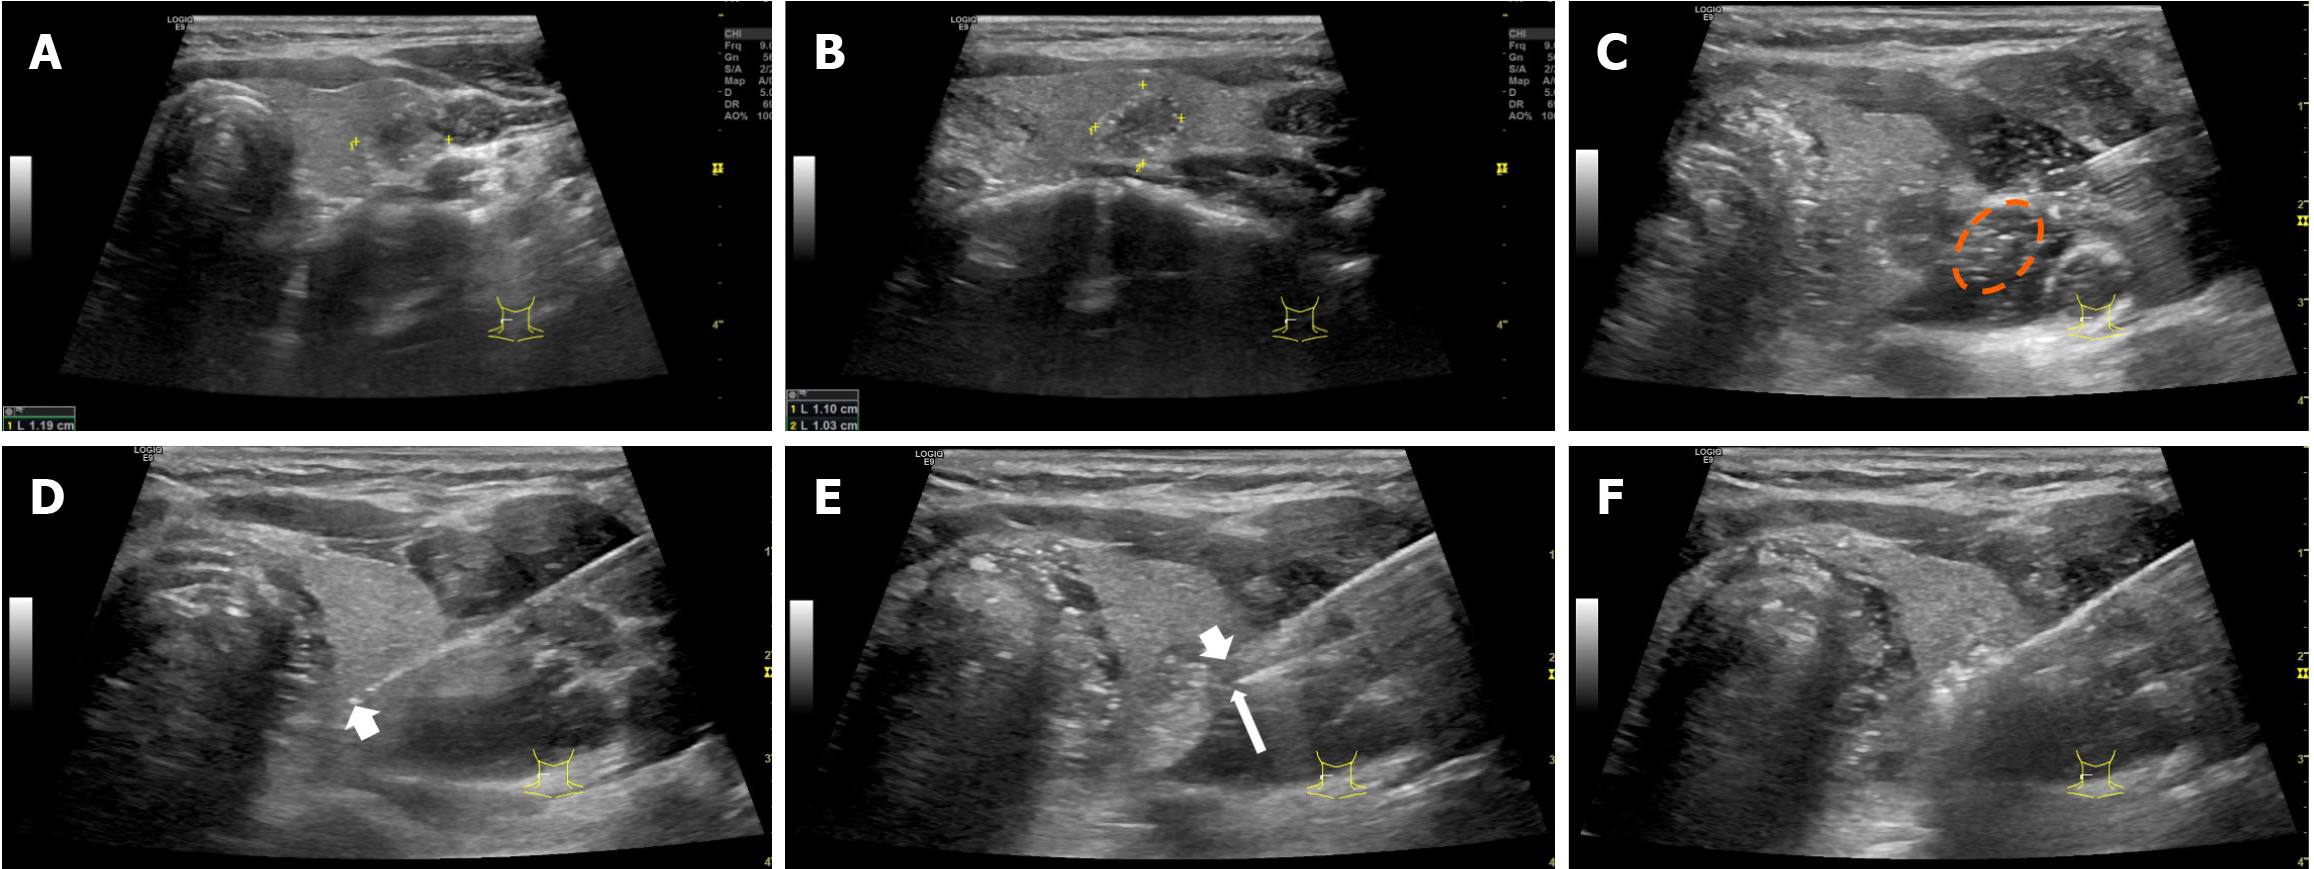

Figure 2 Thermal field management during radiofrequency ablation in a 31-year-old woman with papillary thyroid carcinoma in the right thyroid lobe.

A and B: Longitudinal and transverse pre- radiofrequency ablation ultrasound images show a hypoechoic solid nodule (1.2 cm × 1.1 cm × 1.0 cm) abutting the thyroid capsule; C: Tissue adhesions from tumor invasion impeded formation of an effective fluid barrier between the capsule and surrounding tissue (orange dashed circle); D: The active needle tip extended ≥ 2 mm beyond the original tumor margin (upper boundary on the image) without penetrating the capsule (thick arrow); E: The hydrodissection needle tip (thin arrow) was placed flush against the capsule at the site of heat leakage along the ablation needle shaft (thick arrow), with continuous injection of isolating fluid; F: Heat generated by the active tip was completely confined within the thyroid lobe, and the patient had no discomfort or hoarseness after the procedure.